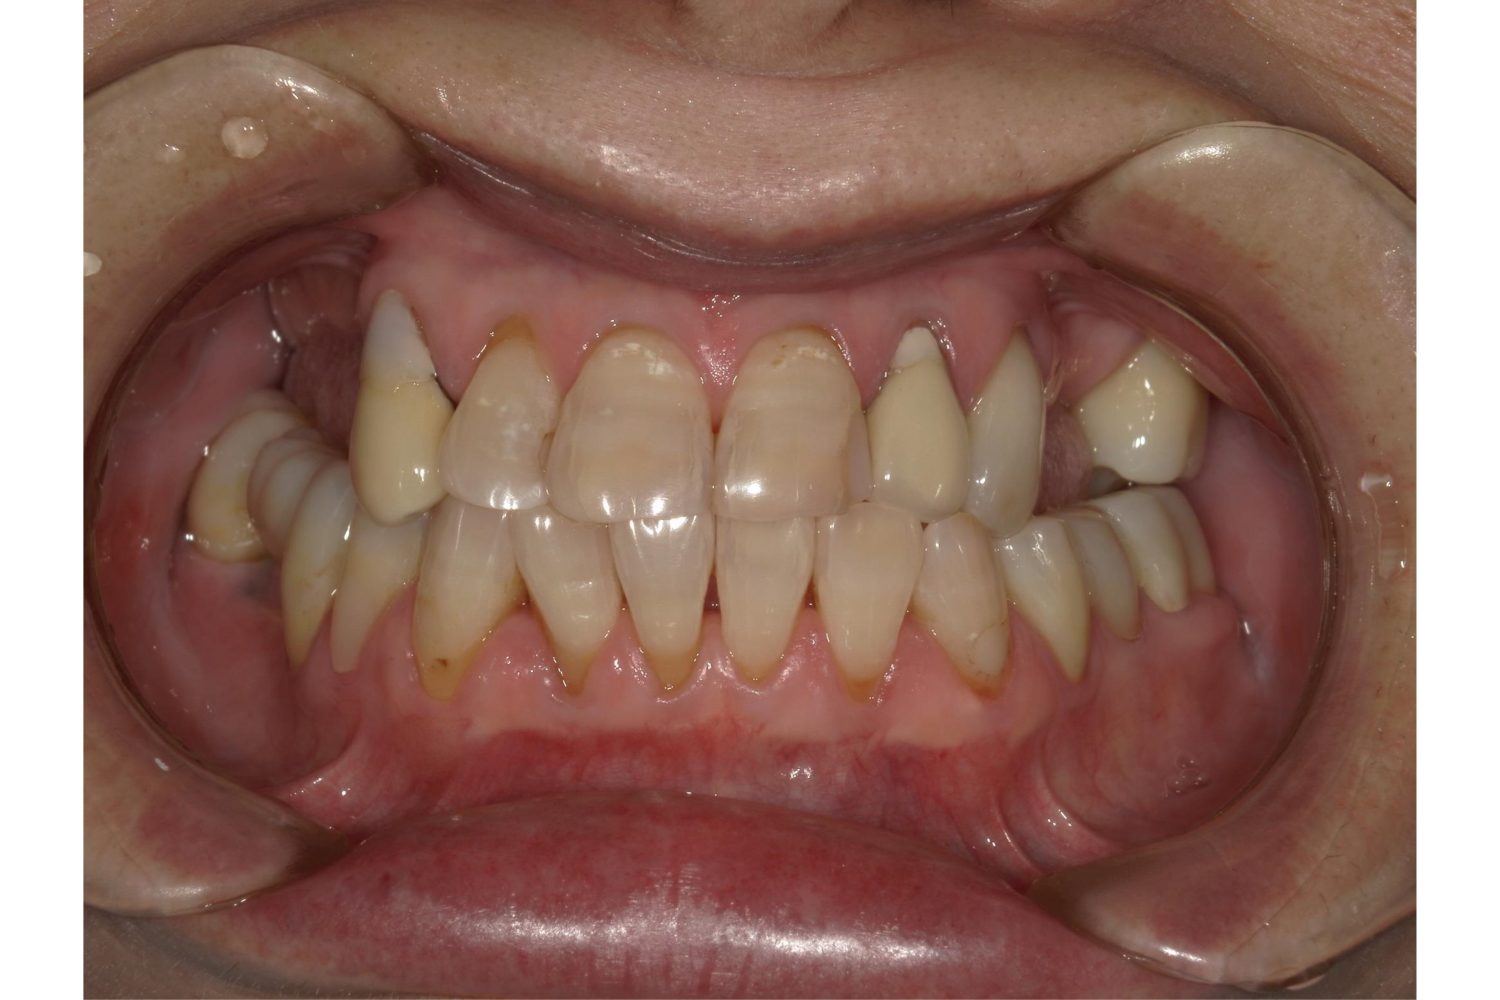

| 主訴 | 歯を白くしたいため来院。 |

| 治療内容 | オフィスホワイトニングを1セット(フッ素塗布、薬剤3回塗布×2日)を行いました。 |

| 想定されたリスク | 人工物(被せ物、詰め物など)はホワイトニングで白くならないため、周囲の天然歯との色の差が生じるリスクがあります。 歯の性状にによってはチョークの様に白くなることがあります。回数を重ねると少しずつ気にならなくなってきます。 |

歯の黄ばみが気になる方へおすすめです。

しみる症状が出にくいように処置の前後でフッ素の塗布を行っています。